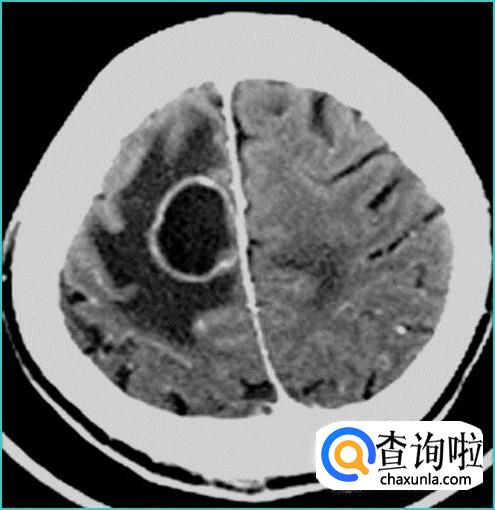

恶性肿瘤来自上皮组织称为“癌”;来源于间叶组织称为“肉瘤”。恶性肿瘤较为严重,发展迅速,生存率低,各个疾病之间生存率跨度比较大。且恶性肿瘤容易转移,转移情况分为4种:直接转移、血道转移、淋巴道转移、种植性转移。恶性肿瘤也要分期,早期比较好治,有痊愈的可能,到了晚期就比较严重,有些可能不得不接受现实,尽量让患者愉快度过最后愉快的时光。

良性肿瘤和恶性肿瘤简单的区别就是看发展是否迅速,是否严重到影响生活,是否有疼痛,肿块大小、硬度、光滑度、活动度都是鉴别点,但是因不同的肿瘤有不同的区别,建议到医院诊断。病理上的区别需要借助仪器,比如CT、X线、造影。需要去医院由影像科进行鉴别,建议不要自行猜测,尽早就医!